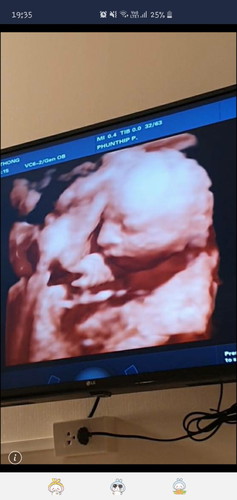

แม่ๆบ้านไหน ซาวด์ 4D กันบ้างคะ เห็นชัดกันมั้ยเอ่ย บ้านนี้ลูกสาวให้ความร่วมมือโชว์หน้าตอน 22 weeks ค่ะ???

จมูกพุ่งมากจ้าคนสวย 😍 อายุครรภ์เท่ากันเลยกำหนดคลอดวันไหนจ้ะแม่